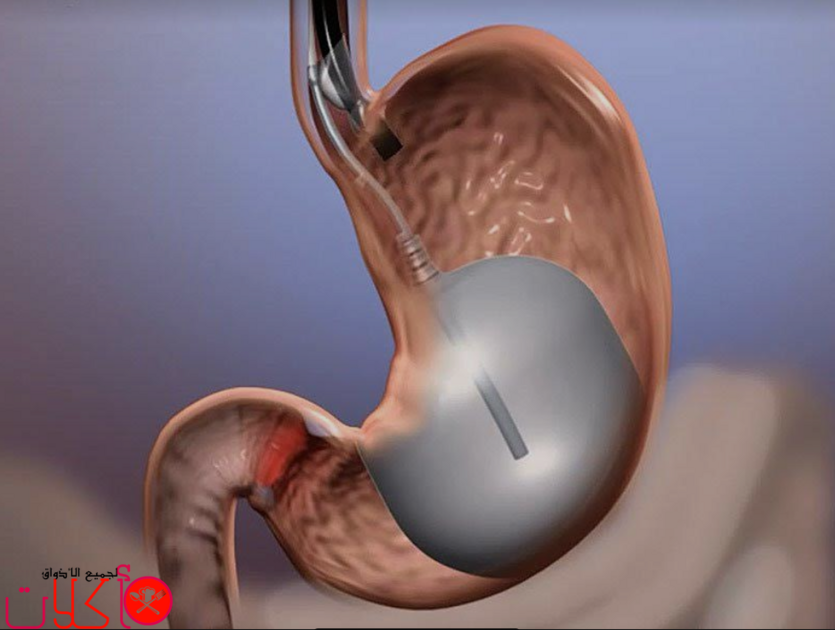

تجربتي مع كبسولة البالون ، كبسولة البالون هي تقنية جديدة لفقدان الوزن تكون عن طريق وضع بالون داخل المعدة قابل للبلع عن طريق كبسولات تؤخذ عن طريق الفم.

كبسولة البالون يكون استخدمها استخدام مؤقت لتسهيل فقدان الوزن لدى البالغين المصابين بالسمنة الذين فشلوا في إنقاص الوزن من خلال النظام الغذائي وممارسة الرياضة. ويكون استخدام كبسولة البالون كعامل مساعد لبرنامج الحمية المعتدلة وتعديل السلوك. ويجب إزالة جميع البالونات بعد 6 أشهر من وضع البالون الأول.

تساعد كبسولة البالون على تخفيف فقدان الوزن عن طريق احتلال مساحة في معدتك لتتناول كمية أقل من الطعام. خلال العلاج، يجب أن تتلقى التغذية المهنية وتعمل على ممارسة التمارين الرياضية لمساعدتك على إجراء تغييرات في نمط الحياة التي تعزز فقدان الوزن. يدعم نظام كبسولة البالون المساعدة في تغيير عاداتك الغذائية والحفاظ على الوزن على المدى الطويل.

1- إجراء بسيط، غير جراحي وسريع. يتم ذلك تحت تأثير التخدير المعتدل ويستكمل في حوالي 20 دقيقة فقط. لا يترك أي ندوب على جسمك.

3- يمكن ترك البالون في معدتك لمدة ستة أشهر ، مما يضمن قدراً مناسباً من الوقت لتكوين عادةً لتناول كميات أصغر.